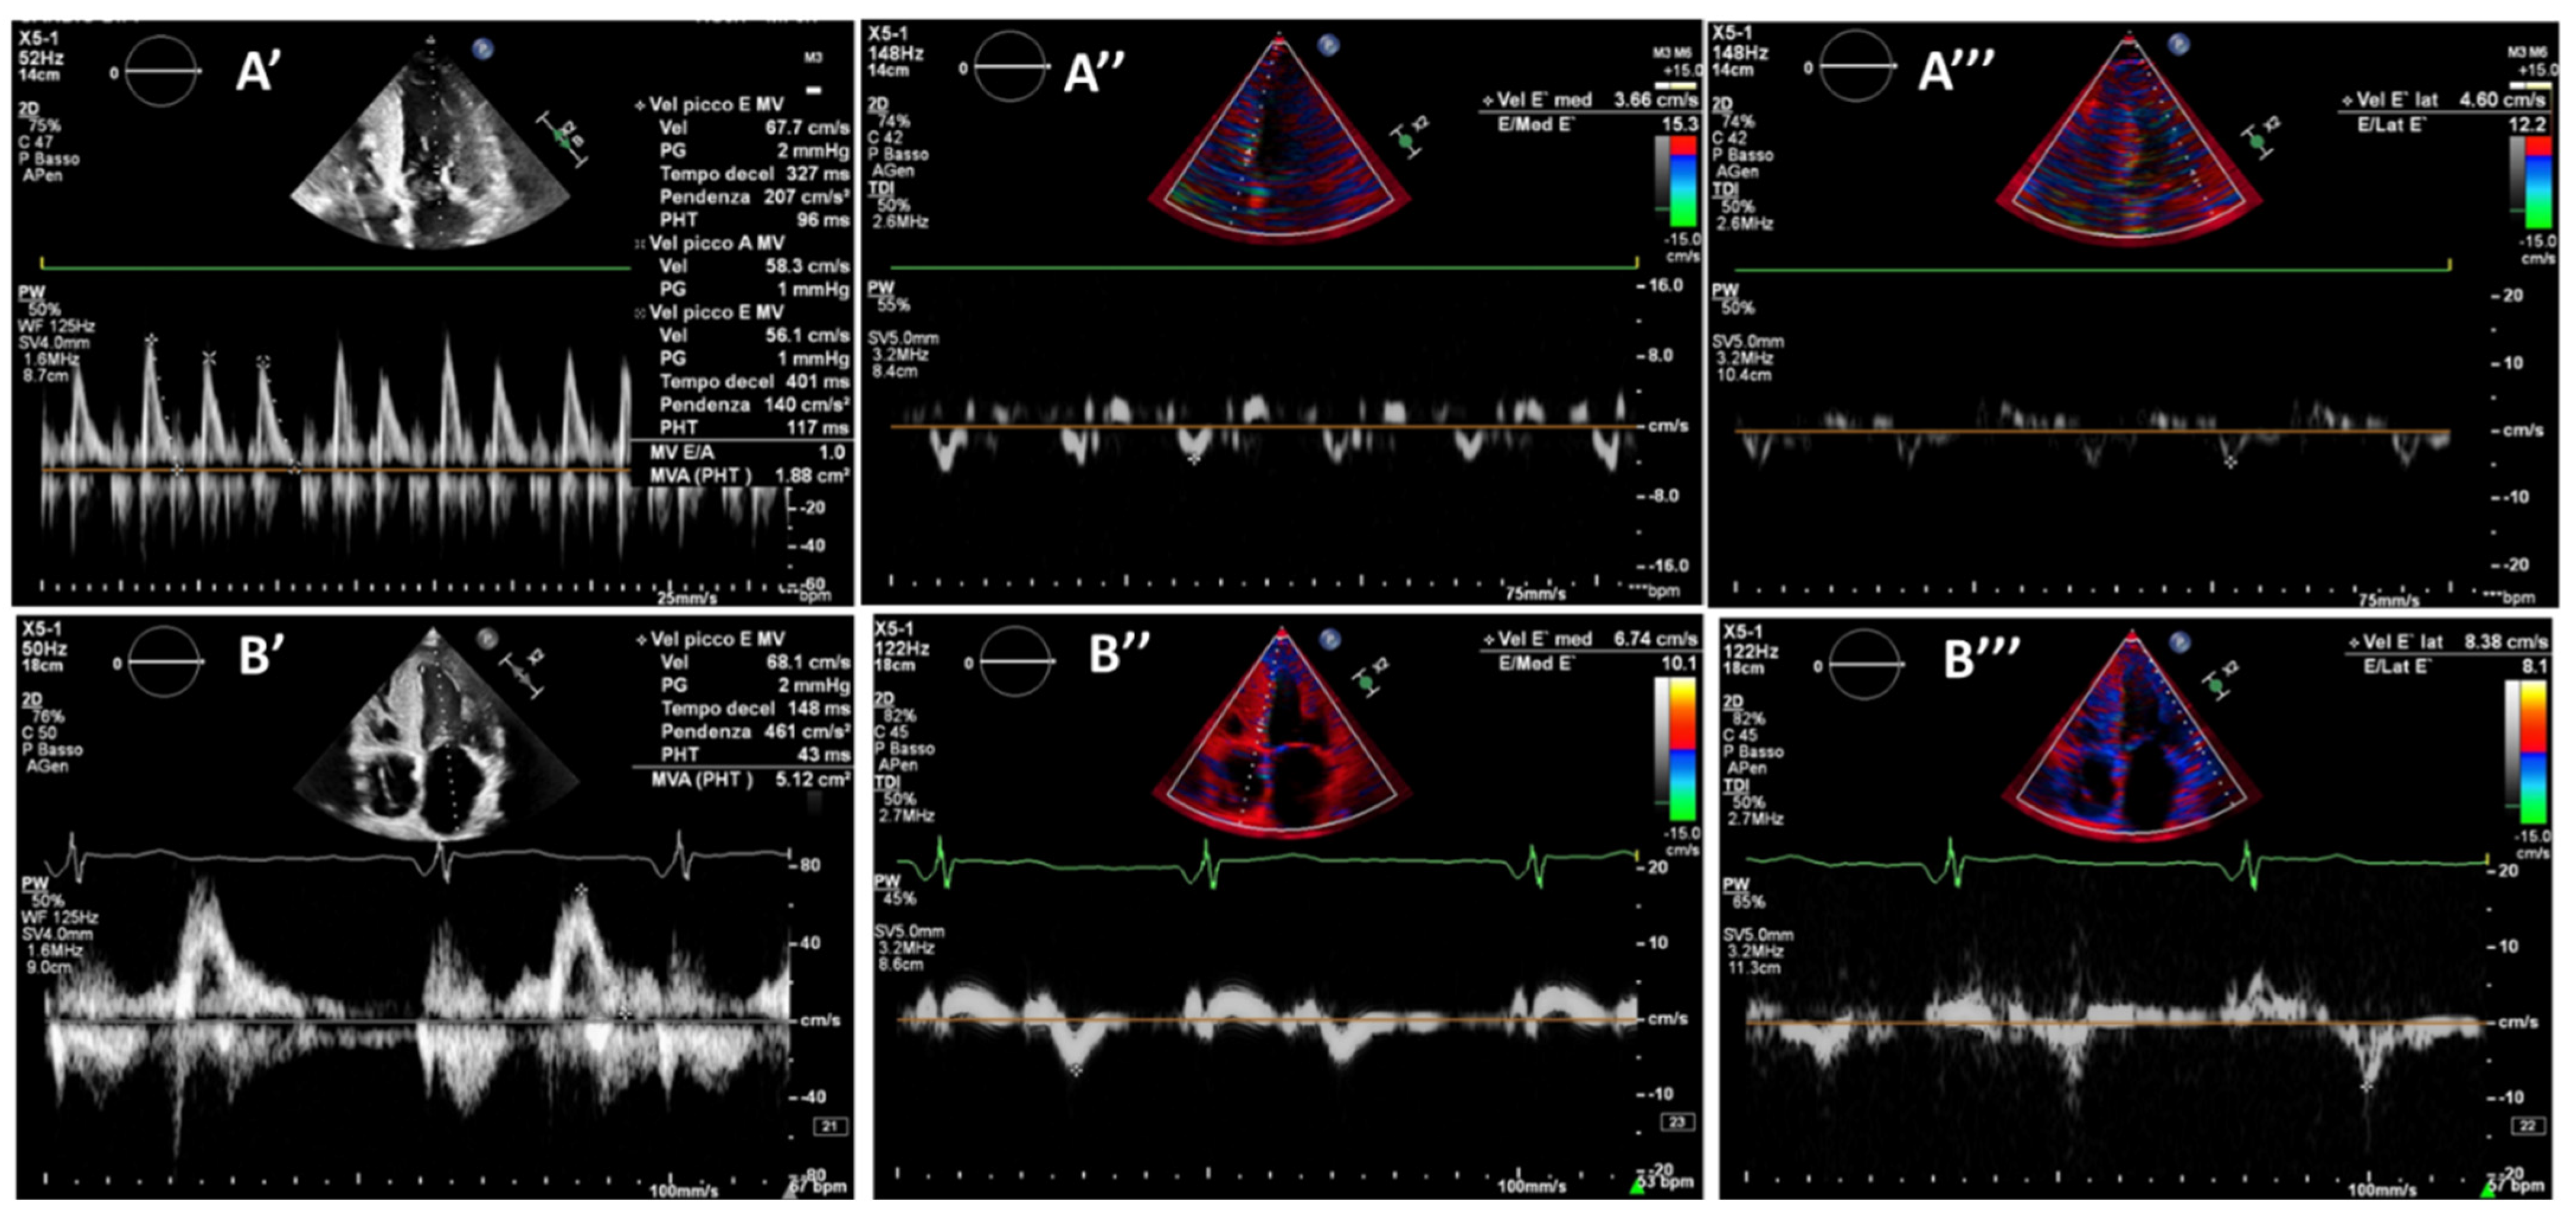

2. Case Report: Wild Type TTR